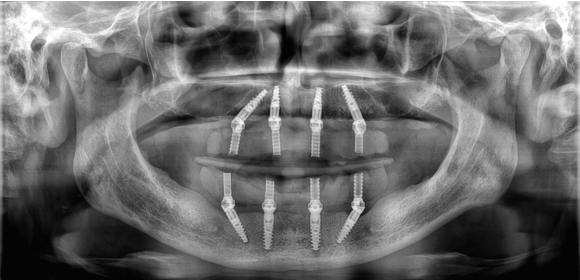

Leczenie metodą All-on-4® pozwala na przeprowadzenie planowej procedury w ciągu jednego dnia. Zazwyczaj polega ona na jednoczasowym usunięciu zębów, wszczepieniu implantów oraz założeniu tymczasowego mostu protetycznego zębów w jeden dzień. Zabieg przeprowadzany jest w warunkach komfortowych dla pacjenta w znieczuleniu miejscowym analgosedacji lub w znieczuleniu ogólnym, w zależności od sytuacji klinicznej lub preferencji Pacjenta.

Wszystkie etapy procedury są szczegółowo planowane z wykorzystaniem technologii cyfrowej 3D oraz dedykowanego oprogramowania. Dzięki zastosowaniu dynamicznej nawigacji X GUIDE lub szablonów chirurgicznych, implantacja odbywa się w optymalnych pozycjach, uwzględniając indywidualną budowę i dostępność tkanki kostnej. Przed przystąpieniem do zabiegu, każdemu pacjentowi zaleca się przeprowadzenie szczegółowej konsultacji, aby omówić wszystkie aspekty procedury.

System DTX Studio umożliwia precyzyjne zaplanowanie pozycji implantów przed zabiegiem. Moduł Dynamicznej Nawigacji Komputerowej X GUIDE lub użycie szablonów chirurgicznychpozwala na implantacje wszczepów w optymalnych pozycjach, które uwzględniają budowę i niedostatki kości.